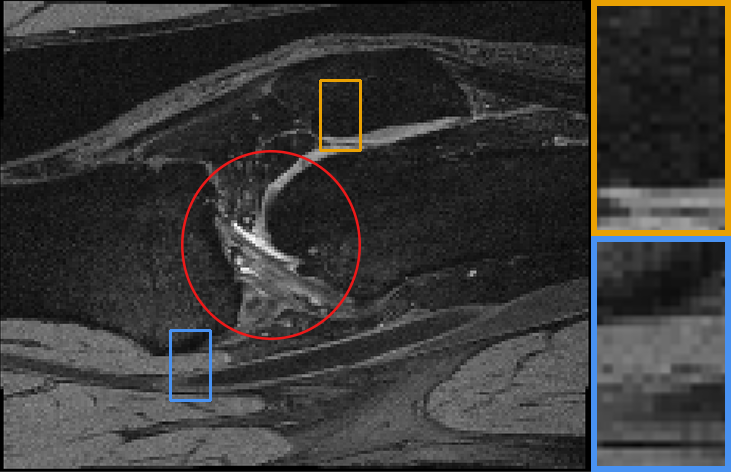

Our representative registration results are given in Fig. 7 and Fig. 8. The first three registration cases in Fig. 7 contain image-to-atlas on T1 brain MR, image-to-image on T1 brain MR and T2 brain MR test pairs. The large deformations in scans make registration challenging and difficult. As a result, all the source images are well aligned to the target. The second three rows in Fig. 8 contain knee T1 MR data, multi-modal data, and lung CT inspiration-expiration images. Although large deformations and intensity differences exist in scans, source images are well aligned to the target, demonstrating our outstanding performance.